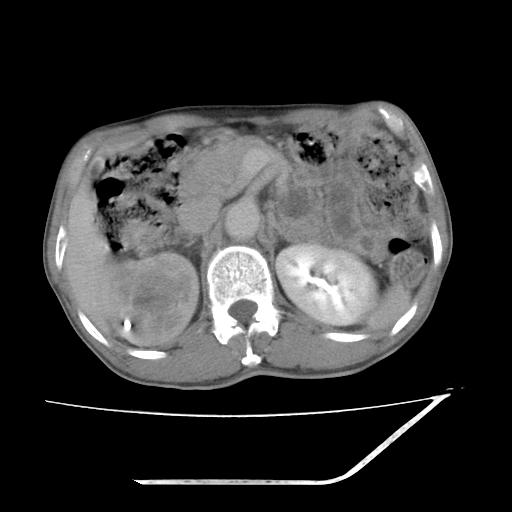

增强

考虑右肾盂癌,肾动脉受侵,右肾功能减退,右肾盂输尿管积水,管壁增厚,考虑种植转移,应该把下面扫完的

支持右侧肾盂癌伴肾静脉瘤栓形成可能性大,右肾结石.肝右叶后段低密度影,不除外转移.

考虑右侧肾盂癌。右侧输尿管扩张未扫描完。

右肾盂旁ca并肾静脉瘤栓形成/肾功能降低。

右肾结石。

右肾盂癌,肾动脉受侵,右肾盂输尿管积水,管壁增厚,考虑种植转移

右肾盂移行细胞癌并右输尿管中段转移.肾积水.

支持 右侧肾盂癌伴肾静脉瘤栓形成可能性大,右肾结石;肝右叶后段低密度影,不除外转移。

1.右侧肾盂癌伴肾盂积水。

2.肾脏功能减退,原因有:(1)肾动脉受侵。(2)肾静脉受侵(3)肾积水,等。本例,肾动脉显影较好,但受压明显;肾静脉无明显显示,受压或静脉癌栓,下腔静脉腔内未见明显充盈缺损。

3.右侧上段输尿管扩张,原因:(1)积水所致;(2)种植。